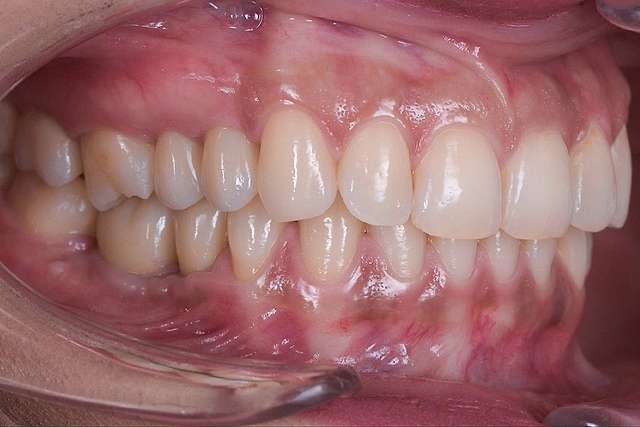

Chirurgia ghidata, ne faciliteaza o pozitie ideal pre-planificata, care nu tine cont doar de os, ci si de o pozitie optima in relatie cu viitorul dinte.Chirurgia ghidata înseamnă o precizie crescuta, care inseamna siguranta mai mare, timp operator mai scazut, si trauma mai mica. De asemenea focusul in acest tip de interventii a migrat spre reconstructia tesuturilor, care e pe termen lung are un impact mult mai mare atat estetic cat si biologic, inserarea implantului in sine fiind trivializata de folosirea ghidului chirurgical. Cazul de fata este un exemplu al acestui tip de abordare.